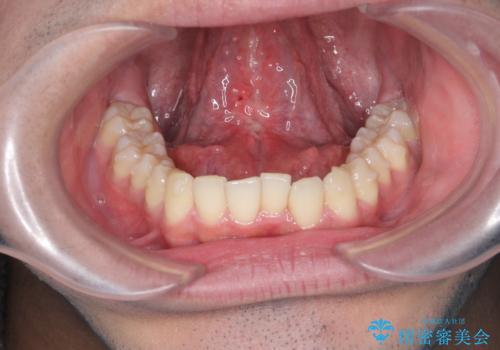

滑舌の改善 舌小帯の形成術

- 舌が動かしづらく、滑舌の改善を希望され来院されました。

舌小帯の形成術を即日で行い、1週間後に抜糸を行います。滑舌の改善を実感され、喜んでいただくことができました.

舌小帯の形成術は約10分程度で終了する小手術です。